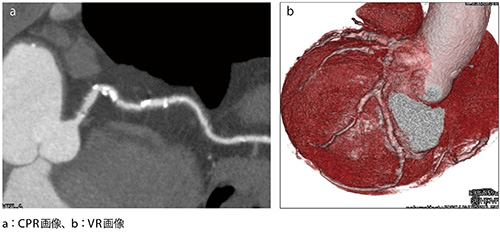

■症例1 息止め不可の状態で撮影した症例